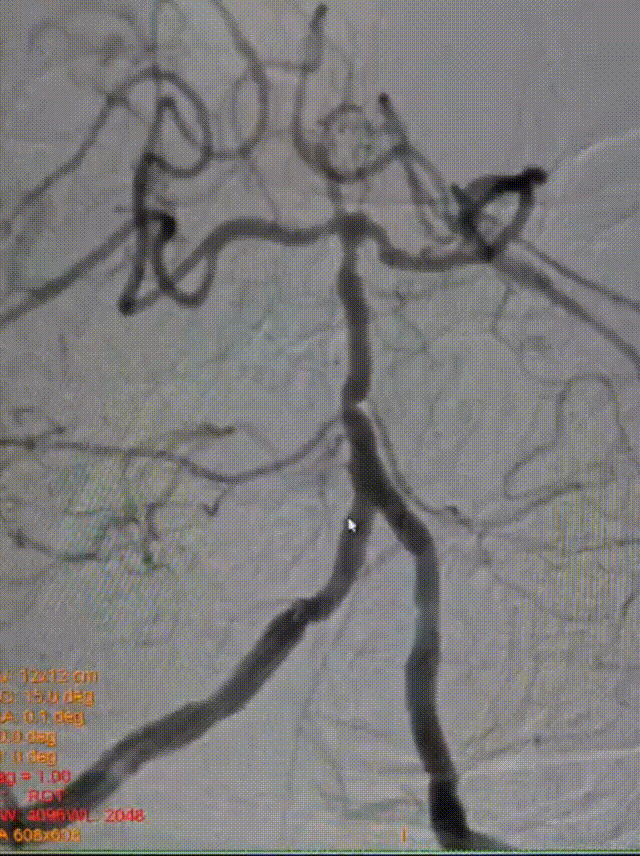

MRA:基底动脉重度狭窄

椎动脉后循环旋转造影

➢造影信息

造影示:右侧优势椎,经右侧椎动脉导弯造影,双侧胚胎型大脑后动脉。

椎动脉V2、V3段迂曲,若不建立良好通路,则后续球囊支架无法到位释放。

基底动脉狭窄位于双侧AICA开口处,且无双侧PICA,其供血区由双侧AICA、SCA分支代偿供血。

术前DSA:双侧后交通动脉开放。

R-VA

L-SUB-VA

术后造影:基底动脉狭窄消失,双侧AICA通畅。